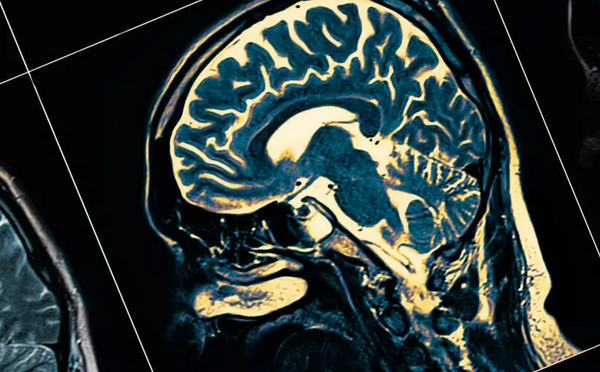

帕金森病是法国第二大常见神经退行性疾病(插图)。 © iStock/sudok1